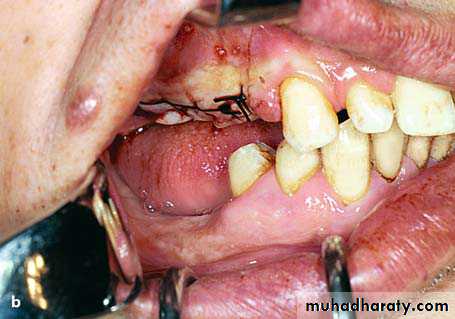

preprosthatic surgery

Diagrammatic illustration (a) and clinical photograph (b) of gross intraseptal irregularities after multiple tooth extractions